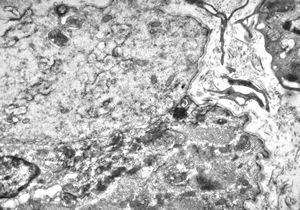

M,56y. | amyloidosis - tendon